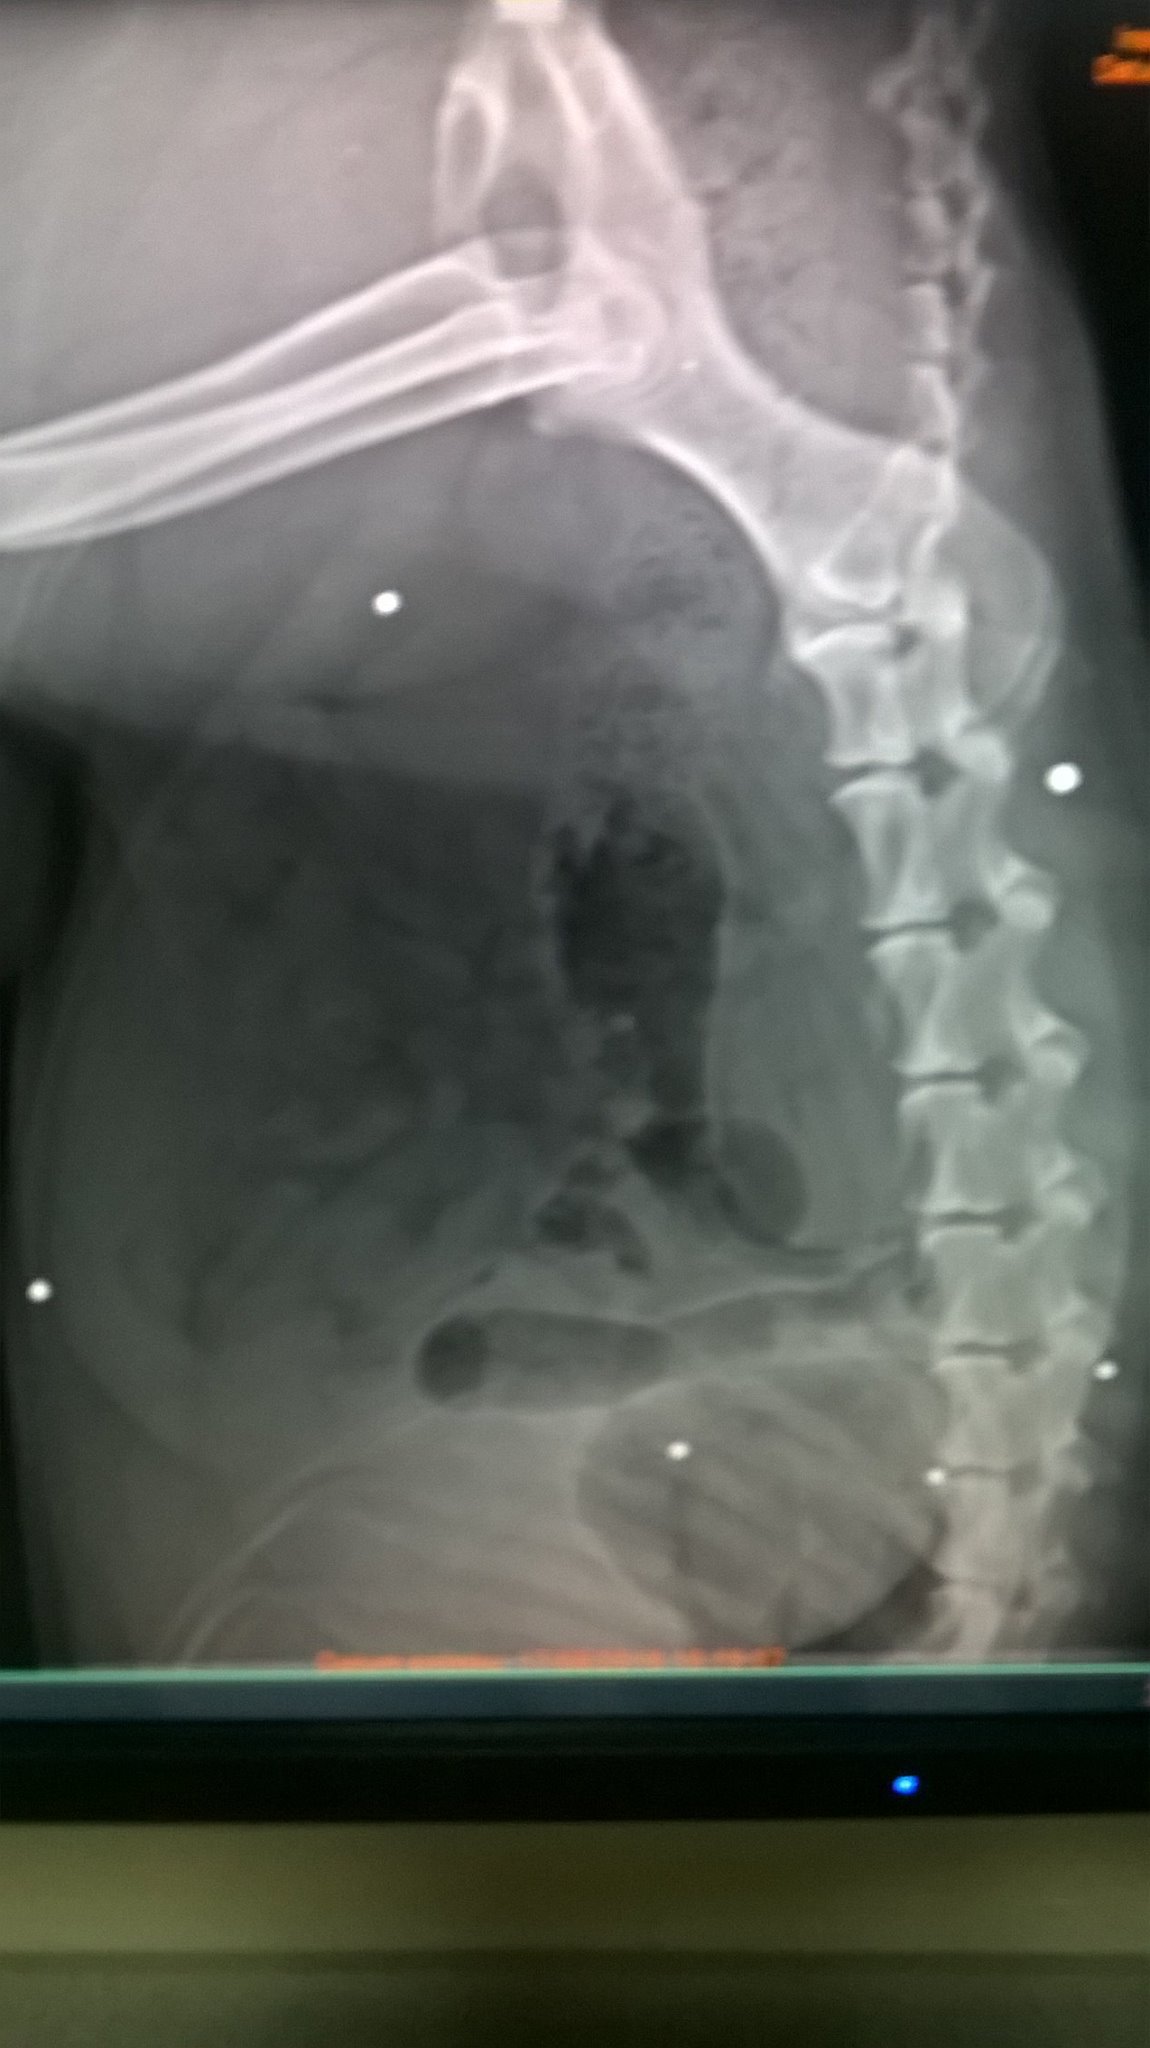

Žije v útulku už niekoľko rokov. V roku 2016 Markus ochorel a bolo nutné RTG. Výsledok vidíte, tie malé biele body sú broky , ktoré má Markus v tele. Netušili sme akým utrpením musel náš miláčik prejsť. Ľudské zlo nemá hranice...